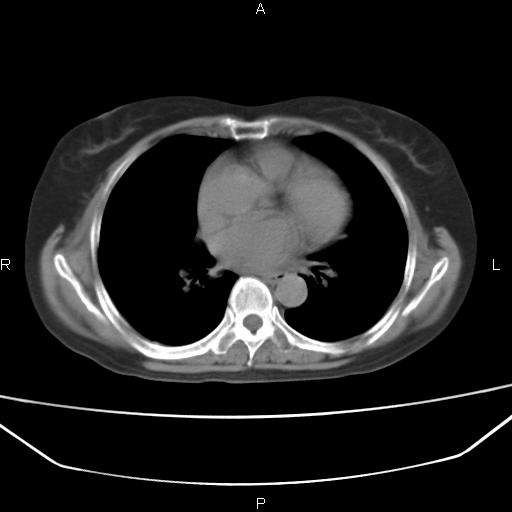

患者,女,66岁。健康体检胸部透视发现右上肺片状阴影。既往无不适,患者自诉三个月前曾有低热病史体温37.5左右一周。用药后缓解。至今无其它不适。请老师们指导指导。

考虑:右肺上叶周围型肺癌(分叶状肿块+砂粒状钙化+胸膜尾征)。

病灶见明显分叶、大小较大(大于3cm?),老年人,多考虑:肺癌,建议穿刺活检。

典型的中心型肺癌,尖段支气管阻塞。

以下是引用dyqct在2010-6-3 9:32:00的发言:[br]考虑:右肺上叶周围型肺癌(分叶状肿块+砂粒状钙化+胸膜尾征)。

不像中央型啊

周围性肺癌,

右肺上叶周围型肺癌可能性大。

考虑:右肺上叶周围型肺癌